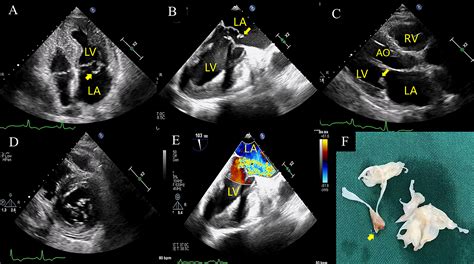

The gold standard for diagnosis is Echocardiography. Specifically, a Transesophageal Echocardiogram (TEE) provides the most detailed view of the valve structures and the flapping leaflet. It allows the medical team to see the ruptured muscle and the severity of the backflow (regurgitation) in real-time.

• papillary muscle rupture echo